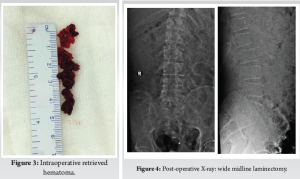

Midline incision was extended and L3–L5 wide laminectomy with hematoma evacuation was done, and drain was placed in situ. The thecal sac was pulsatile. Intraoperatively drain was also kept in situ to avoid further hematoma if any.

Post-operative period was uneventful with improvement in constitutional symptoms, right ankle dorsiflexion, and EHL power to grade 3/5. Deep vein thrombosis (DVT) prophylaxis was given in form of DVT pumps until lower limb strengthening exercises were started. Post-operative radiograph confirmed wide laminectomy. (Fig. 4) Foley’s catheter was kept in situ on discharge and removed after 1 month postoperatively. The patient was discharged on day 15 in stable condition with training in limb strengthening exercises and was made to stand bedside. During 6-month follow-up period, the patient showed improvement in power of ankle dorsiflexion and EHL by 3 grade and bowel bladder symptoms improved. Following 1 year, the patient had resumed his daily activities and was walking without support.